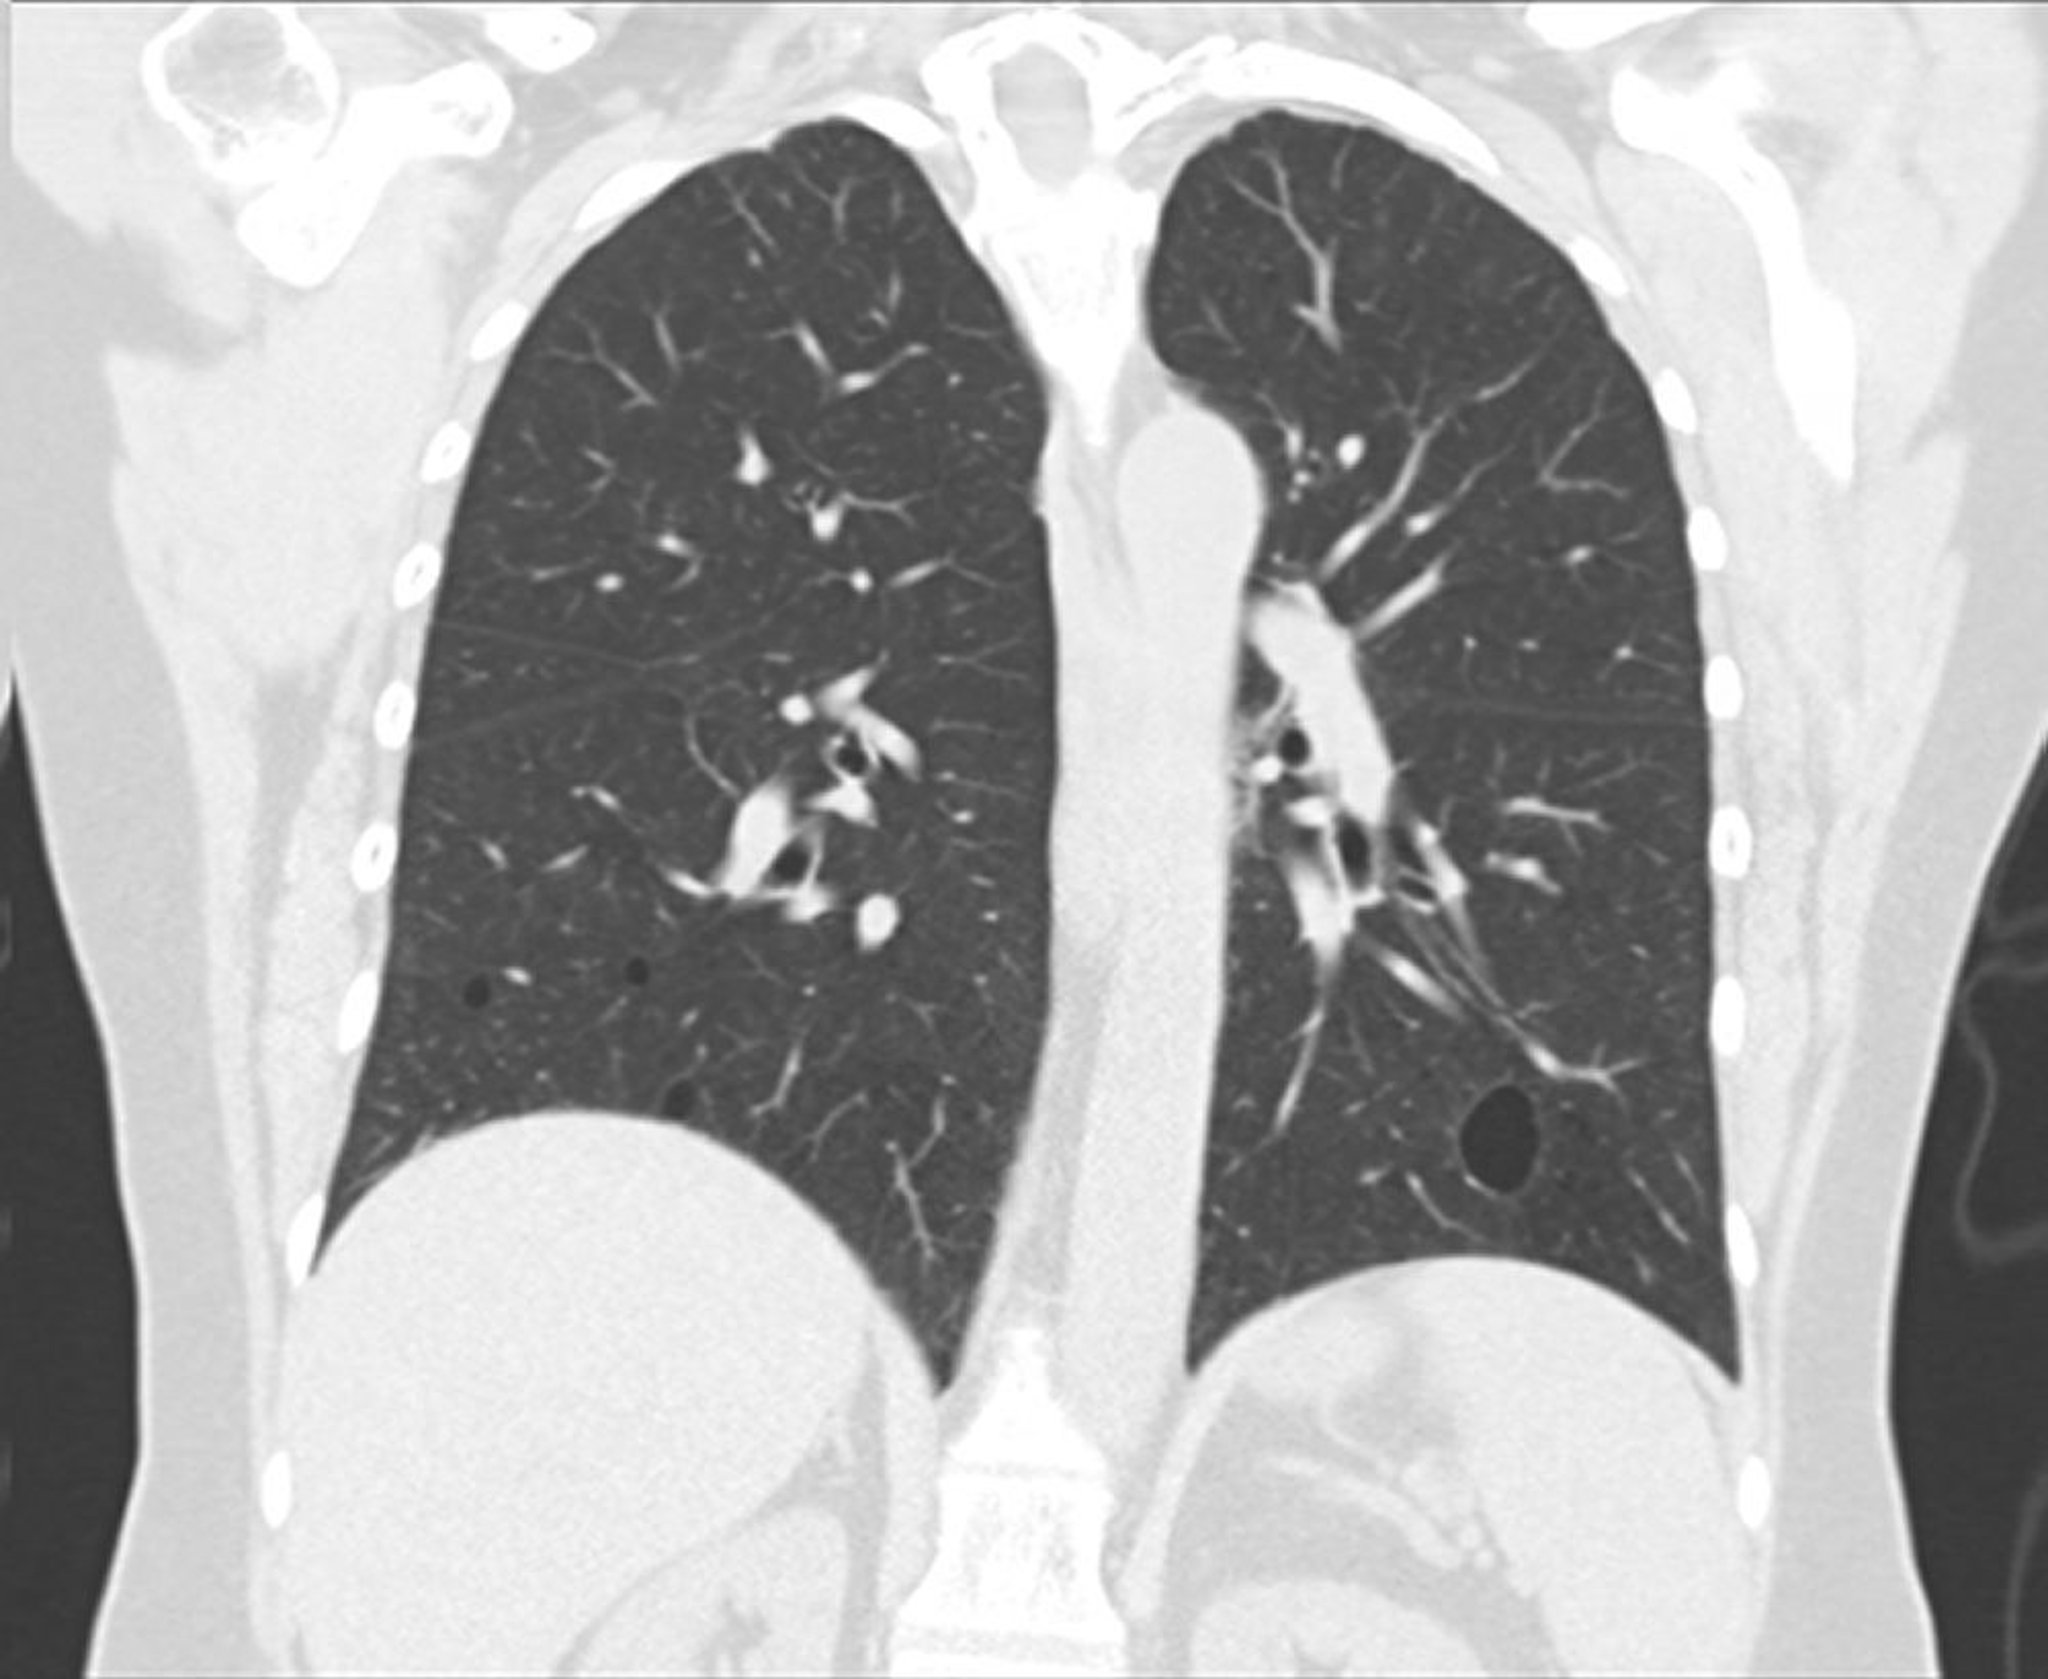

Лимфоцитарная интерстициальная пневмония

На этом рисунке изображена вторичная лимфоцитарная интерстициальная пневмония вследствие синдрома Шегрена. На данном срезе коронарных артерий, полученных при КТ, можно увидеть хорошо очерченные кисты в нижних долях с обеих сторон.